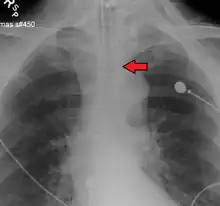

Ideally, at least one of the methods utilized for confirming tracheal tube placement will be a measuring instrument. Waveform capnography has emerged as the gold standard for the confirmation of tube placement within the trachea. Other methods relying on instruments include the use of a colorimetric end-tidal carbon dioxide detector, a self-inflating esophageal bulb, or an esophageal detection device.[35] The distal tip of a properly positioned tracheal tube will be located in the mid-trachea, roughly 2 cm (1 in) above the bifurcation of the carina; this can be confirmed by chest x-ray. If it is inserted too far into the trachea (beyond the carina), the tip of the tracheal tube is likely to be within the right main bronchus—a situation often referred to as a "right mainstem intubation". In this situation, the left lung may be unable to participate in ventilation, which can lead to decreased oxygen content due to ventilation/perfusion mismatch.[36]